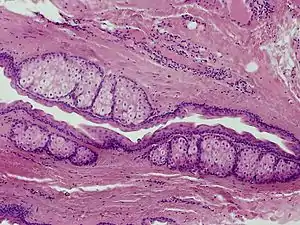

Steatocystoma multiplex

Steatocystoma multiplex, is a benign, autosomal dominant congenital condition resulting in multiple cysts on a person's body. Steatocystoma simplex is the solitary counterpart to steatocystoma multiplex.[2]

Steatocystomas are thought to come from an abnormal lining of the passageway to the oil glands (sebaceous duct).